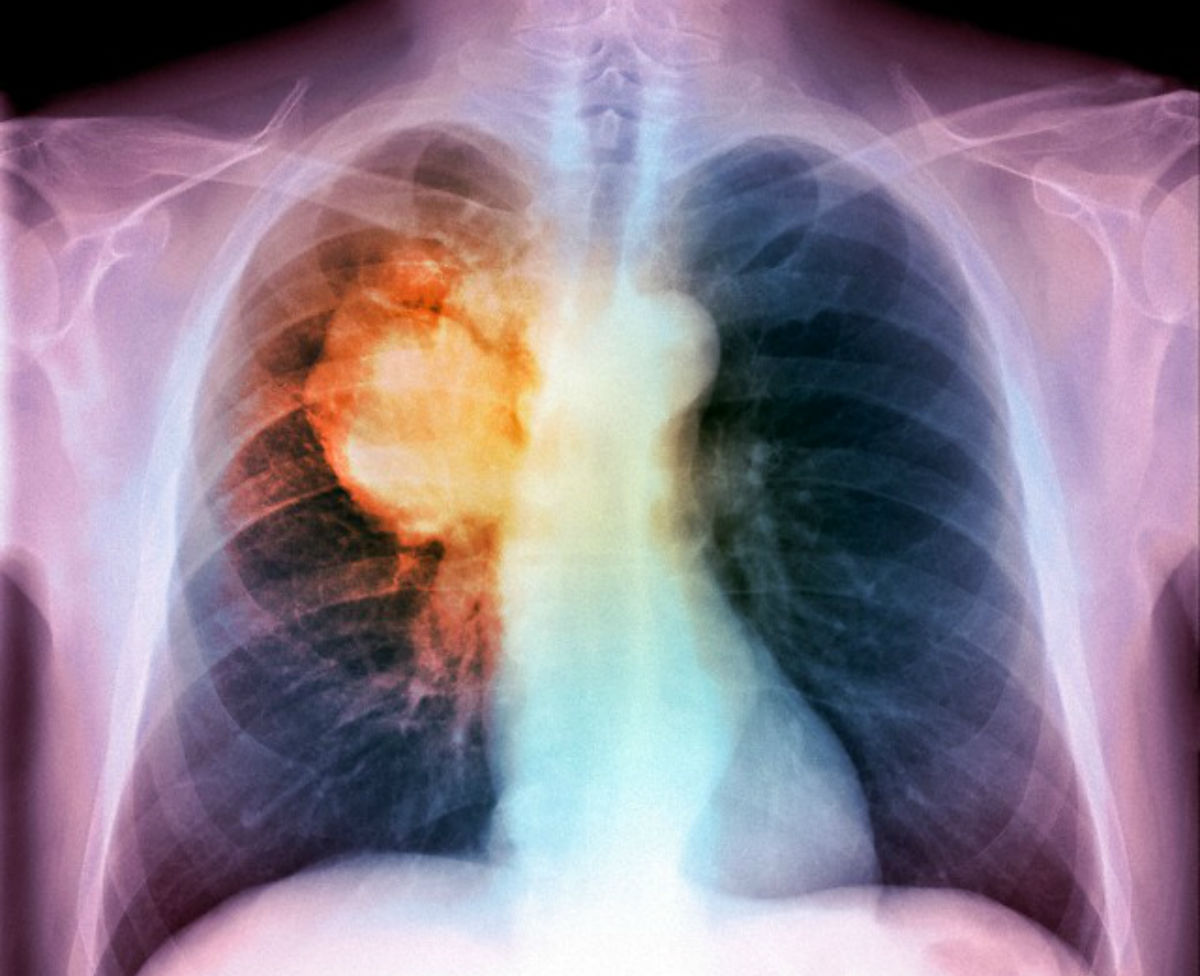

STATI UNITI – Secondo uno studio condotto dalla Stony Brook University di New York e pubblicato sulla rivista “Nature”, il 90% dei tumori è riconducibile a fattori esterni evitabili. Tra questi, si trovano sostanze tossiche, inquinamento, alcol, fumo, radiazioni e un generale stile scorretto di vita. Questa nuova teoria ribalta quindi quella della “cattiva sorte”, pubblicata proprio quest’anno. “I fattori ambientali hanno un ruolo importante e le persone non possono nascondersi dietro la sfortuna. Non possono fumare e poi dire che si sono ammalati per sfortuna” ha spiegato Yusuf Hannun, ricercatore dell’università di Stony Brook.

Per gli esperti, quindi, l’aumento della percentuale di tumori non può più essere legato solo a semplici anomalie nella divisione cellulare. L’équipe ha inoltre analizzato precedenti ricerche sugli immigrati dai paesi con basso rischio i quali sviluppano maggiori possibilità di contrarre malattie oncologiche nel nuovo Paese. Per alcuni tipi di cancro, come quello dell’intestino, della pelle e di testa-collo, i fattori di rischio sembrano quindi più ambientali che genetici.

Solo tra il 10 e il 30% dei casi i tumori sono invece dovuti ad anomalie del corpo o alla sfortuna. Molti specialisti hanno accolto con favore la tesi proposta dall’Università di New York. La strada da fare, però, è ancora molta: “Resta un problema, dato che non tutti i rischi estrinseci sono stati identificati e non tutti potrebbero essere evitabili” ha spiegato lo stesso Hannun.